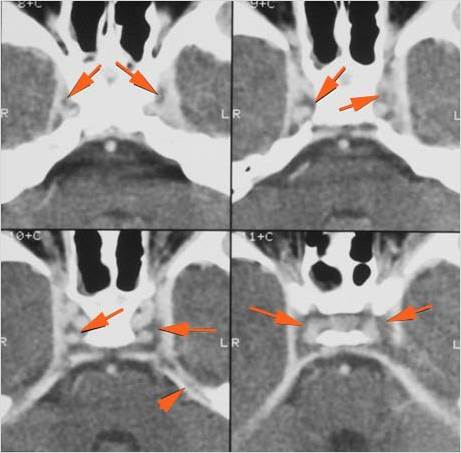

Intracranial

There is a subperiosteal fluid collection or abscess along the boney walls of the anterior or middle cranial fossa. [Yes/No]

There is an epidural fluid collection or abscess along the boney walls of the anterior or middle cranial fossa. [Yes/No]

There is a subdural fluid collection or abscess along the boney walls of the anterior or middle cranial fossa. [Yes/No]

There is a subdural fluid collection or abscess along the falx cerebri or within the tentorium. [Yes/No]

There is evidence of thrombus, thrombophlebitis or other occlusive or inflammatory process of the cortical veins, sphenoparietal sinus or sagittal sinus. [Yes/No]

There is evidence of thrombus, thrombophlebitis or other occlusive or inflammatory process of the cavernous sinus. [Yes/No]

There is evidence of inflammation of the distal internal carotid artery. [Yes/No]

There is evidence of an infectious aneurysm. [Yes/No]

There is brain edema specifically involving the frontal and temporal lobes. [Yes/No]

There is cerebritis specifically involving the frontal and temporal lobes. [Yes/No]

There is brain abscess specifically involving the frontal and temporal lobes. [Yes/No]

There is likely meningitis, meningoencephalitis with complicating hydrocephalus or brain herniation. [Yes/No]